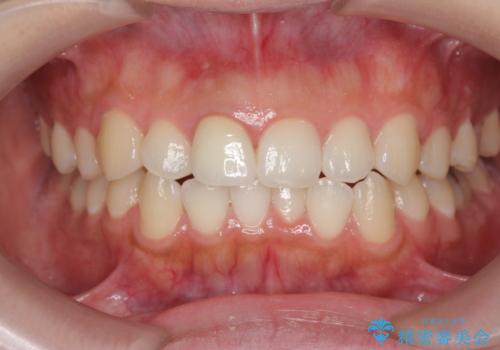

歯ぐきにできものができた 前歯の色調改善

- 歯ぐきに、にきびのようなものができ治らない、と治療を希望され来院されました。

歯髄の検査、X線検査より神経の失活が確認されたので、根管治療・ファイバーコア築盛 ・ジルコニアクラウンの製作、と治療を進めます。

根管治療を行ったことで、歯ぐきのできものは治癒し再発をしなくなりました。